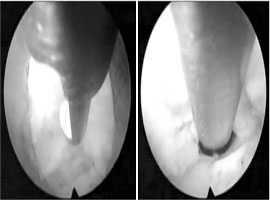

최근들어 발목이나, 팔꿈치, 어깨 모두 내시경을 이용한 수술이 인기가 많아졌는데 그 이유는 바로 개방창이 작아서

회복이 빠르기 때문입니다. (빠르게 느껴집니다.) 이러한 유행을 따라서 작은 관절에 해당하는 척추도 요즘에는 내시경으로 수술을 시도하고 있습니다.

개방창이 작아 미용적으로는 확실히 효과가 있으며, 시술 같은 수술이라고 생각하면 될 정도로 작은 흉터만 남게 됩니다. 하지만 수술자의 실력에 따라 오히려 내부의 근육의 파열이나 안의 조직, 인대들의 파괴가 될 수 있습니다. 오히려 개복술이 더 빠르고 예후가 좋을 수도 있습니다. 절개 후 근육을 적절하게 젖히고 접근시 직접적으로 척추 뼈를 보면서 수술하는 것이 신경을 건드리거나 실수할 확률이 더 적을 것이기 때문입니다. (물론 절개하는 과정에서 관절경에 비해 과도한 출혈이나 근육손상 등이 있을 수 있습니다. )

새로운 방식이라 관심이 많이 가지만, 견관절, 슬관절과 같이 관절내 공간 자체가 무척 좁기 때문에 어느정도 가동범위의 감소로 인한 어려움이 있을 것이라 생각이 됩니다. (물론 그만큼 중요한 해부학적 구조물이 크게 없을 수 있습니다.)